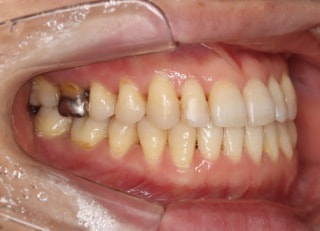

治療後パノラマレントゲン

歯根のパラレリングは良好です。顎関節に問題はありません。

治療後顎関節レントゲン

CO-CR位置の改善が認められます。